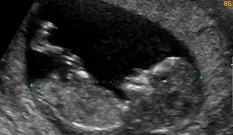

Ainda é possível fazer o ultrassom do primeiro trimestre e, neste caso, tudo o que explicamos na semana anterior segue valendo. Na maioria das pacientes, os primeiros exames da gravidez já foram feitos — já passamos por um dos principais momentos em que se verificou que está tudo bem.

| Já passamos por um dos grandes momentos da gravidez, o ultrassom do primeiro trimestre, no qual se verificou que estava tudo bem. |